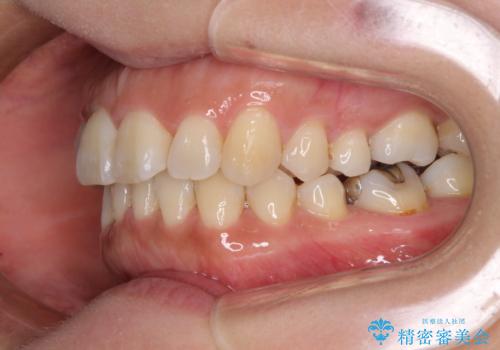

軽度な歯列不正 インビザライン・ライトによる矯正治療

- 上下前歯の叢生を気にして来院された患者様です。

費用を抑え、期間もあまりかけずに治療をしたいとのことで、インビザライン・ライトを用いて矯正治療を行うこととしました。

インビザライン・ライトは、製作できるアライナーの枚数に制限があるため、移動可能な量に限りがあります。

一方で、半年から1年程度で治療を終えることができるため、軽度の歯列不正の患者様には大変お勧めです。